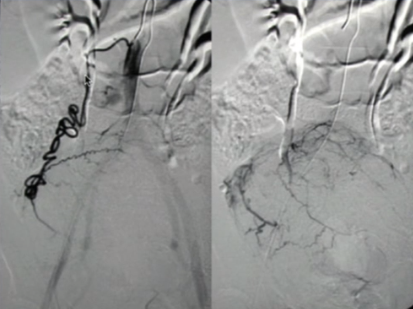

所有年龄超过 40 岁的患者, 卵巢受损 14%-43% 研究中闭经发生率(15%)与单纯UAE报告相似,可能与患者年龄(≥45岁)及卵巢储备自然下降有关。 ![]() 50岁,长期因子宫肌瘤导致月经出血过多,痛经和贫血。 子宫肌瘤栓塞术前,显示双侧子宫动脉发育不全,子宫肌瘤双侧卵巢动脉。 经皮股动脉穿刺双侧卵巢动脉栓塞,先500μm-700μm emboSphere 微球 术后4周,和6月的中短期随访,月经正常,子宫容积减少,贫血纠正,无卵巢功能衰竭。但看起来非灌注容积较少。 术后9月,由于子宫肌瘤持续存在,患者自己希望绝经,行全子宫和双侧卵巢切除术 术后病理,子宫内可见栓塞微粒伴有坏死,卵巢内也见栓塞微粒,但卵巢功能未受损。

双侧卵巢动脉栓塞术在选择性病例(如子宫动脉发育不全、卵巢动脉为主要血供)中是可行且有效的。

未引起卵巢功能衰竭,说明技术安全。

需长期随访以进一步验证其安全性。